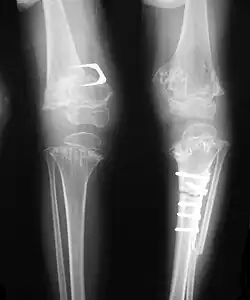

Accurate assessment of plain radiographic findings remains an important contributor to diagnosis of pseudoachondroplasia. It is noteworthy that vertebral radiographic abnormalities tend to resolve over time. Epiphyseal abnormalities tend to run a progressive course. Patients usually suffer early-onset arthritis of hips and knees. Many unique skeletal radiographic abnormalities of patients with pseudoachondroplasia have been reported in the literature.[2][7][4]

• Together with rhizomelic limb shortening, the presence of epiphyseal-metaphyseal changes of the long bones is a distinctive radiologic feature of pseudoachondroplasia.

• Dysplastic/hypoplastic epiphyses especially of shoulders and around the knees.

• Metaphyseal broadening, irregularity and metaphyseal line of ossification. These abnormalities that are typically encountered in proximal humerus and around the knees are collectively known as “rachitic-like changes”.

• Radiographic lesions of the appendicular skeleton are typically bilateral and symmetric.